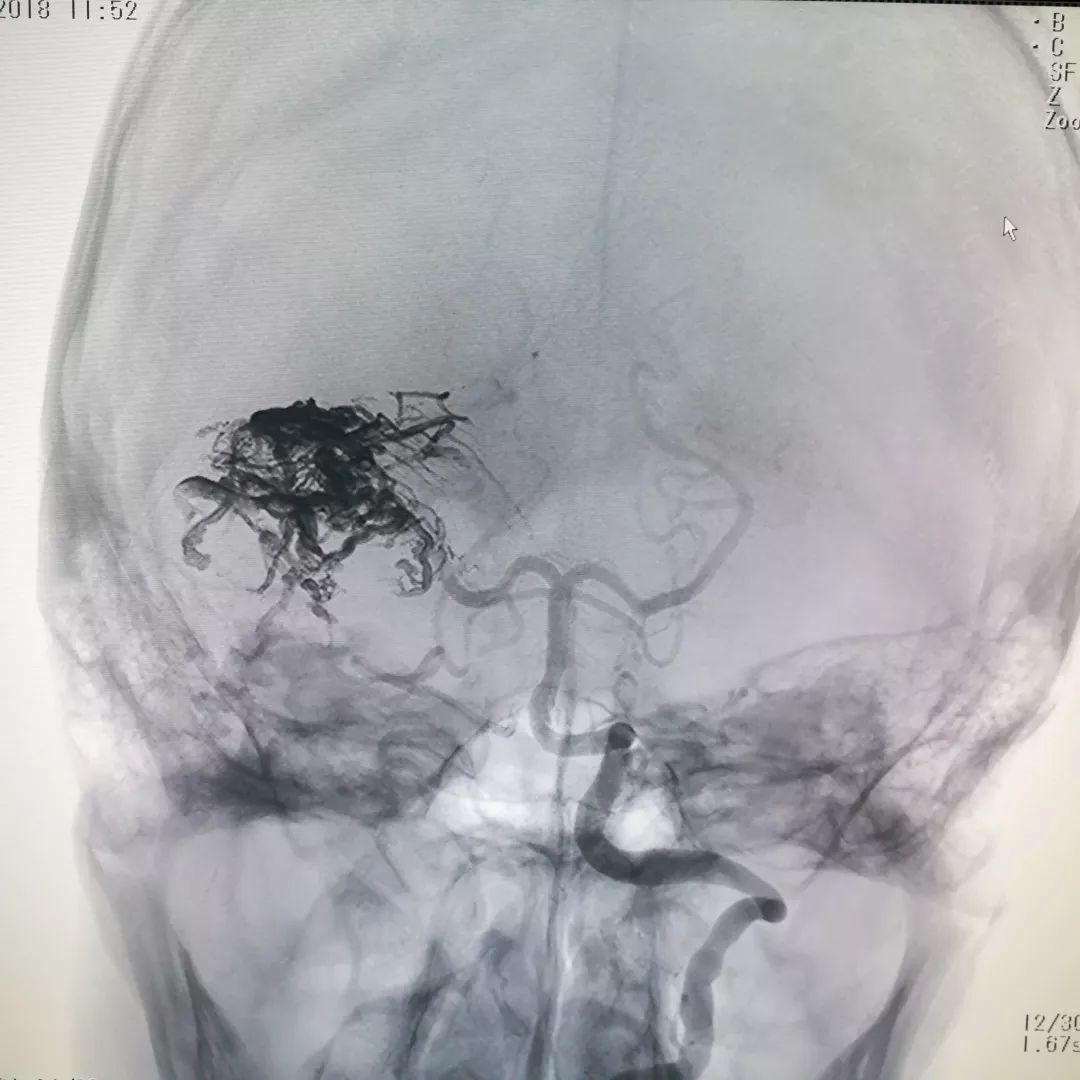

脑血管造影证实肿瘤血供极其丰富,血窦样结构充满血液,供血动脉粗大

通过介入栓塞,向肿瘤内注入栓塞物质(下图),填充并堵塞血窦,阻止流入到肿瘤内,从而降低手术

复查造影提示肿瘤内大部分血窦被堵塞,肿瘤内血液供应明显减少,从而达到降低手术风险减少术后并发症的目的